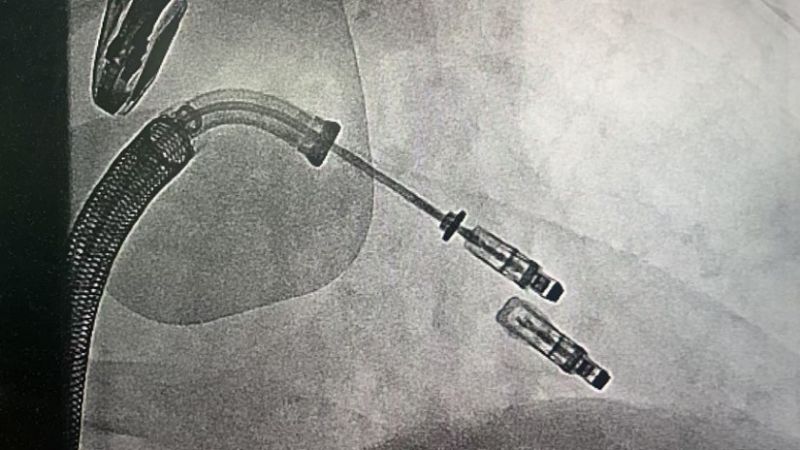

手術于11月4日下午進行,通過股靜脈穿刺送入夾合器,在食道超聲實時引導下,精準植入2枚瓣膜夾修復二尖瓣。整個過程歷時約2小時,術中出血量僅50ml。術后次日,患者即可下床活動,復查顯示EF提升至46%,二尖瓣返流面積縮小至3.0cm2,左心房縮小至66mm,胸悶、氣短癥狀明顯緩解。

2.精準定位:在食道超聲和X線引導下,將夾合器送達二尖瓣位置,通過夾合病變瓣膜減少返流;